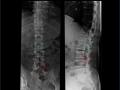

Metástase de câncer de mama para pedículo vertebral

raio-X de coluna ver...